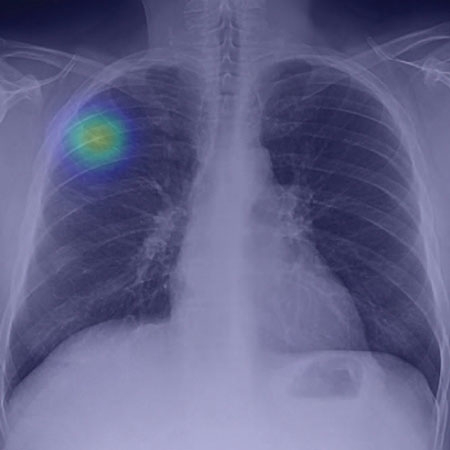

Interview with Puneeth Iyengar, MD, PhD, author of Accelerated Hypofractionated Image-Guided vs Conventional Radiotherapy for Patients With Stage II/III Non–Small Cell Lung Cancer and Poor Performance Status: A Randomized Clinical Trial